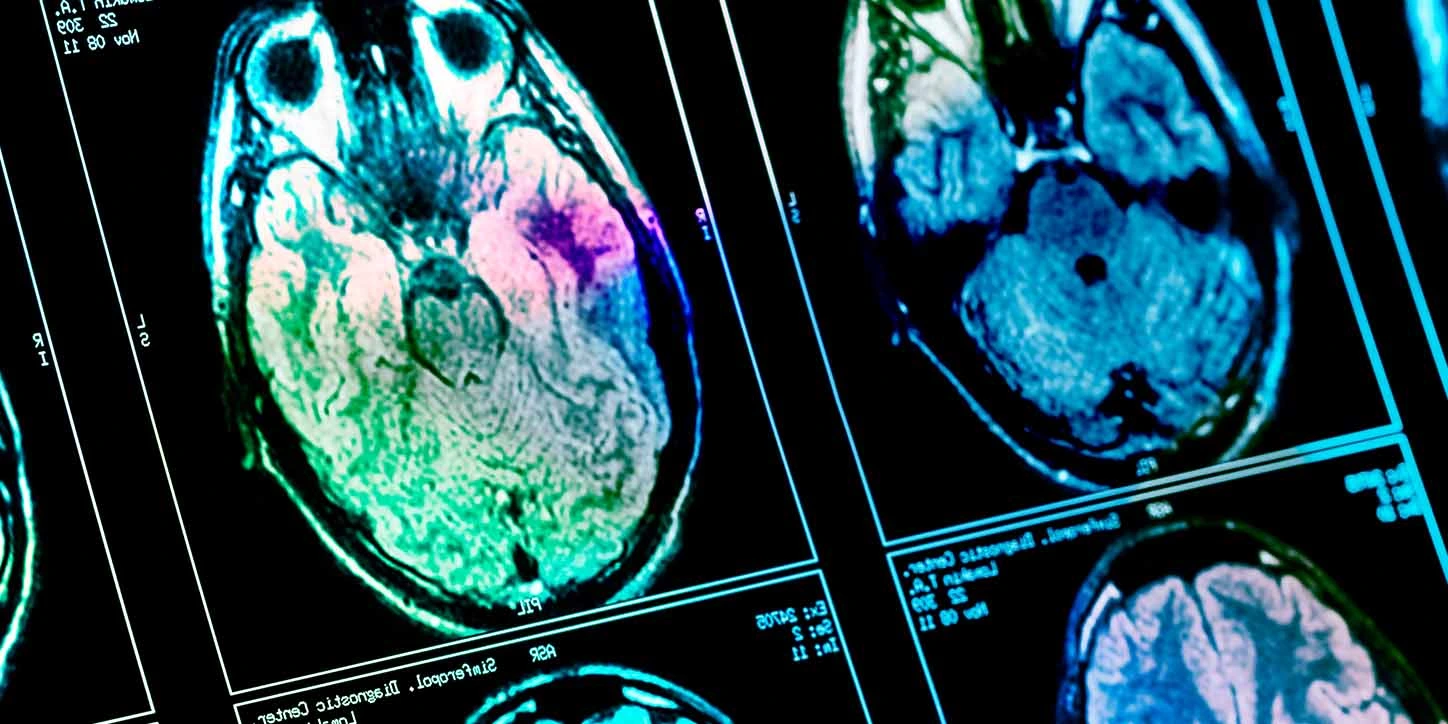

Exames clínicos, laboratoriais, de imagem e, quando necessário, testes genéticos ajudam a diferenciar cada caso.